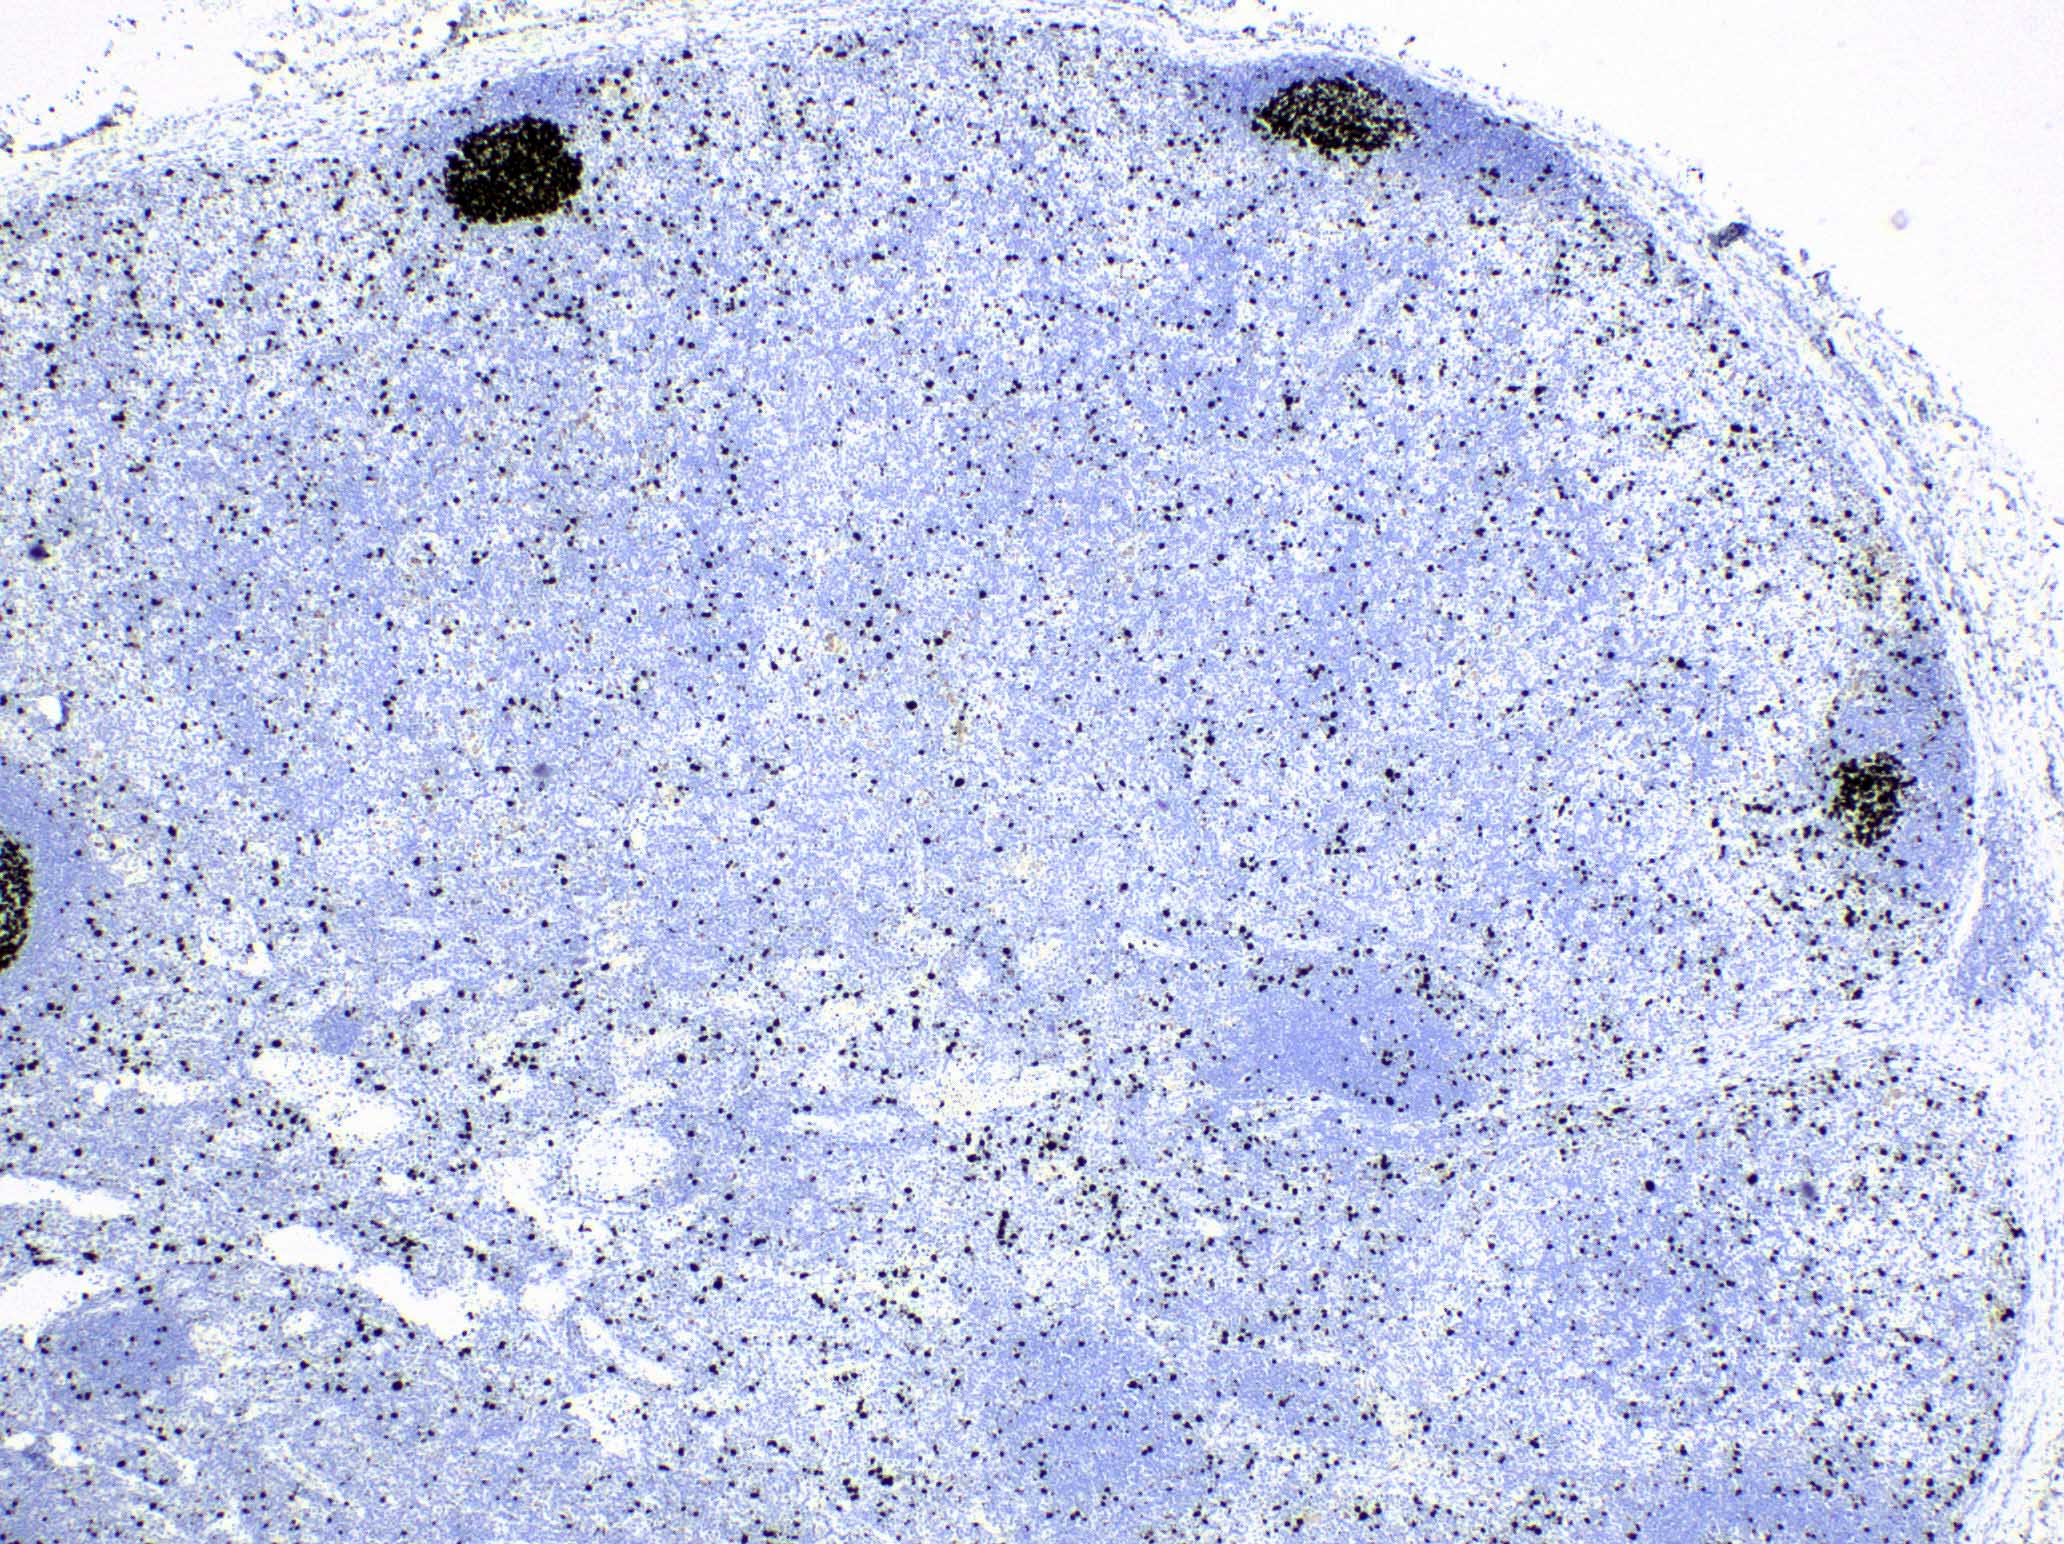

Microscopic (histologic) images

Contributed by Ingrid Tam, M.D., M.Sc., Emina Emilia Torlakovic, M.D., Ph.D. and Nikhil Sangle, M.D. (Case #396)

Positive stains

- S100, CD1a, CD207 / langerin: Langerhans cells

- CD4 and CD8: typically there is great predominance of CD4+ T cells over CD8

- S100, MUM1 / IRF4: interdigitating dendritic cells (Am J Surg Pathol 2022;46:1514)

- CD68: histiocytes and dendritic cells